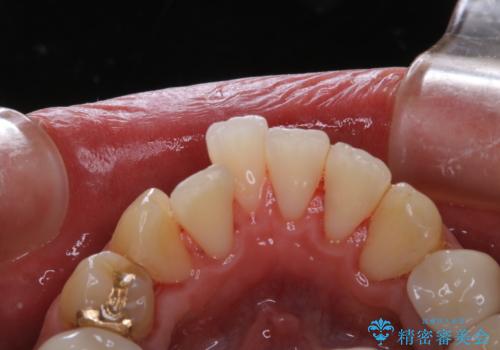

前歯の着色をPMTCできれいに